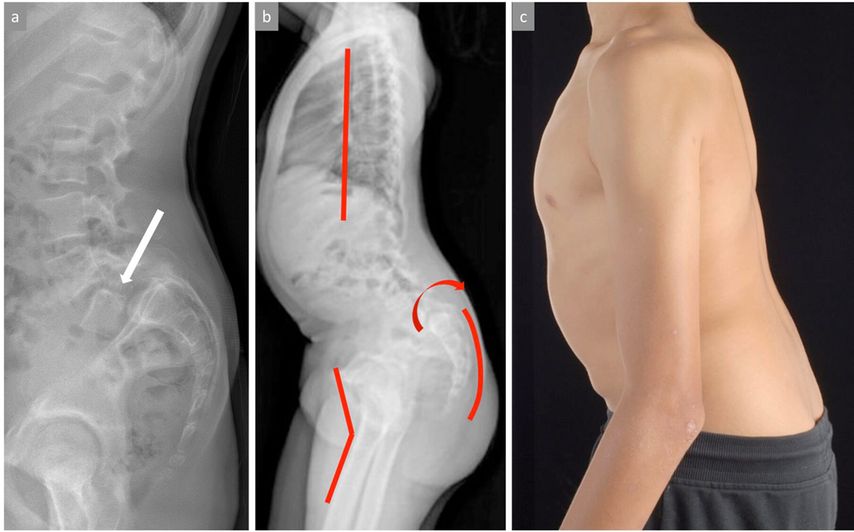

Nebst einer allgemeinen dynamischen und statischen orthopädischen Untersuchung muss eine dezidierte Beurteilung der Wirbelsäule einschliesslich einer neurologischen Untersuchung durchgeführt werden. Typisch für die Spondylolyse sind reproduzierbare, meist klar umschriebene und als stechend beschriebene lumbosakral lokalisierte Schmerzen bei forcierter Extension (Reklination) der LWS. Neurologische Auffälligkeiten sind selten nachweisbar. Bei Vorliegen einer Spondylolisthese kann manchmal eine Stufe zwischen den Dornfortsätzen der unteren LWS getastet werden. Ein hochgradiges Wirbelgleiten führt durch die zunehmende segmentale Kyphosierung zu einer relevanten Störung des sagittalen Profils der Wirbelsäule mit typischen, klinisch objektivierbaren Kompensationsmechanismen wie Abflachung der Brustwirbelsäule, Retroversion des Beckens/Sakrums bis hin zu zunehmender Hüft- und Kniebeugung zur Aufrechterhaltung der sagittalen Gesamtbalance (Abb. 2).

Abb. 2: Bild (a) zeigt ein stehendes seitliches Röntgenbild der Lendenwirbelsäule (LWS) mit hochgradiger Spondylolisthese von LWK5 gegenüber SWK1. Die Abbildungen (b) und (c) zeigen radiologisch und klinisch die mit der Zeit möglichen Kompensationsmechanismen bei hochgradigem Wirbelgleiten mit Abflachung der Kyphose der BWS, Retroversion des Beckens sowie Hüft- und Knieflexion zum Erhalt der sagittalen Balance